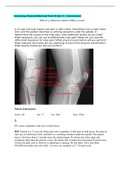

• Assessing Musculoskeletal Pain Week 8 | Assessment Min of 3 reference dated within 5 years A 15-year-old male reports dull pain in both knees. Sometimes one or both knees click, and the patient describes a catching sensation under the patella. In determining the causes of the knee pain, what additional history do you need? What categories can you use to differentiate knee pain? What are your specific differential diagnoses for knee pain? What physical examination will you perform? What ana...